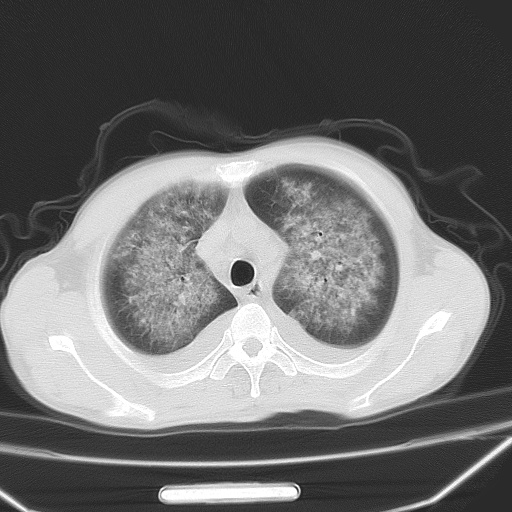

男、42岁、咯血3天。既往有甲亢、贫血、血尿蛋白尿史多年。血象:wbc:6.   中性粒:70.6%。

双肺堆成磨玻璃影,双测胸腔积液。考虑:肺水肿、间质性肺炎、真菌感染、ards、hiv感染、肺出血。

双肺野对称性磨玻璃影,分布于内中带,双侧胸水,患者有咯血。

双肺野广泛对称性磨玻璃影、实变影,以肺门为中心,主要分布于内中带,符合典型肺泡性肺水肿;伴双侧胸腔少量游离积液。结合患者既往病史且咯血就诊,支持多因素(尿毒症等)所致之肺水肿、肺出血、胸水;影像表现暂不考虑心源性水肿,且症状也不太符。需密切随诊结合临床治疗等进一步明确。